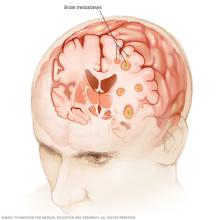

A brain tumor can form in the brain cells (as shown), or it can begin elsewhere and spread to the brain. As the tumor grows, it creates pressure on and changes the function of surrounding brain tissue, which causes signs and symptoms such as headaches, nausea and balance problems.

Brain tumors can begin in the brain. These are called primary brain tumors. Sometimes, cancer spreads to the brain from other parts of the body. These tumors are secondary brain tumors, also called metastatic brain tumors.

Brain metastases

Brain metastases happen when cancer begins elsewhere in the body and spreads (metastasizes) to the brain.

Cancer that spreads to the brain

Secondary brain tumors happen when cancer starts somewhere else and spreads to the brain. When cancer spreads, it's called metastatic cancer.